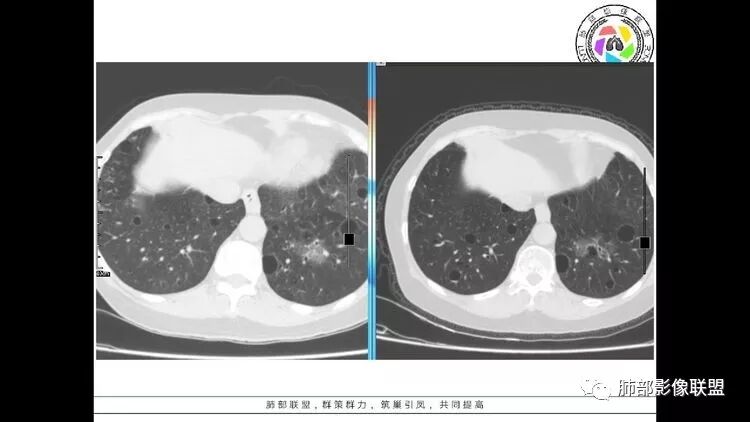

老年女性,眼炎入院,血常规正常,双肺多发囊状影,病变随机分布,形态单一,与血管关系密切,考虑LIP。左下肺混合GGO,边界尚清,贴近囊腔,鉴别腺癌。炎症指标无异常暂不考虑感染性病变。

胸CT:1.双肺多发囊性变,以中下肺为主,病变边缘可见肺动脉,部分囊内可见分隔及肺动脉,双下部分肺野周围可见小叶中心结节及树丫征。

2 左肺上叶尖后段 右肺上叶前段 右肺下叶外基底段 结节影,边界清楚,可见柔软毛刺,左肺下叶后基底段混合密度影。

患者中年女性,因右眼红痛1天就诊。胸CT:双肺多发囊性变及结节影,囊以中下肺为多,部分囊内可见分隔及肺动脉,结节部分为实性,部分为混合性,边缘光滑,未见明显毛刺、棘突、胸膜牵拉及血管集束征象。双中下可见支气管扩张及树丫征。淋巴结无明显肿大。综合考虑:一元淋巴细胞间质性肺炎。多元鉴别肺腺癌并转移等恶性病变。

中年女性,双肺多发囊性变,以中下肺为主,病变边缘可见肺动脉,部分囊内可见分隔及肺动脉,左肺上叶较大结节,可见分叶、月牙铲,左肺下叶、右肺中叶磨玻璃病灶,边界清楚,内有空泡,结节,可见尖后段 右肺上叶前段 右肺下叶外基底段 结节影,边界清楚,纵隔淋巴结肿大,

中年女性,因“角膜炎”入院,自用眼液2年,(眼干?)肺部:双肺多发类圆形薄壁气囊+实性结节+GGO,下肺分布为主,纵隔淋巴结肿大,考虑淋巴系统增殖,LIP可能性大,可能继发于干燥综合症;左肺下叶的混合磨玻璃结节形迹可疑,边界清晰,内部疑似空泡,扩张扭曲支气管,极像肺癌,伴双肺转移?待排吧

左肺下叶混杂密度病灶,其内可见空泡,周围ggo清楚,考虑浸润性腺癌。双肺散在多发薄壁囊腔和实性结节,以胸膜下及血管旁分布位于,气囊可见血管贴边征,双肺小叶间隔及中央间质增厚,局部可见磨玻璃影及树芽征,纵隔内淋巴结肿大,考虑LIP

综上,考虑左下肺浸润性腺癌+LIP

双肺多发大小不等囊腔,可见薄壁,部分囊腔内可见血管影,伴双肺多发结节,结合患者眼病及类风湿病史,考虑LIP可能大。另左肺下叶磨玻璃结节,边界清晰,内可见空泡,伴纵膈多发肿大淋巴结,不除外浸润性腺癌可能。

LIP影像重要线索一句话:

双肺下叶分布为主的间质改变(磨玻璃影、小叶间隔增厚)、散在气囊影(常有血管贴边)、边界不清小结节